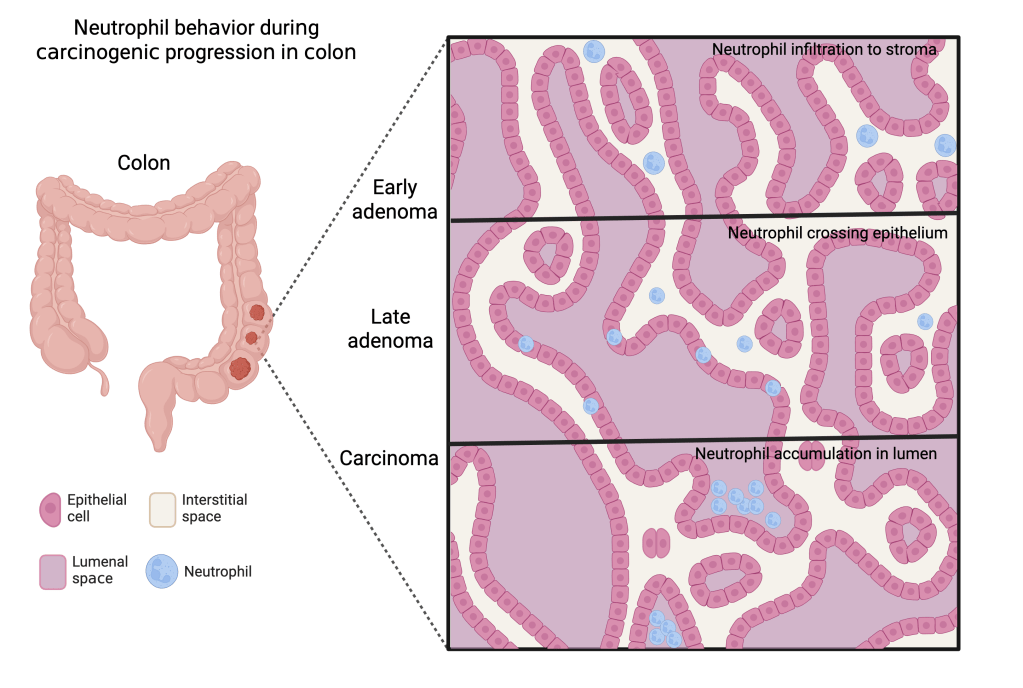

Heiser CN, Simmons AJ, Revetta F, McKinley ET, Ramirez-Solano MA, Wang J, Kaur H, Shao J, Ayers GD, Wang Y, Glass SE, Tasneem N, Chen Z, Qin Y, Kim W, Rolong A, Chen B, Vega PN, Drewes JL, Markham NO, Saleh N, Nikolos F, Vandekar S, Jones AL, Washington MK, Roland JT, Chan KS, Schürpf T, Sears CL, Liu Q, Shrubsole MJ, Coffey RJ, Lau KS. Molecular cartography uncovers evolutionary and microenvironmental dynamics in sporadic colorectal tumors. Cell. 2023 Dec 7;186(25):5620-5637.e16. doi: 10.1016/j.cell.2023.11.006. PMID: 38065082; PMCID: PMC10756562.